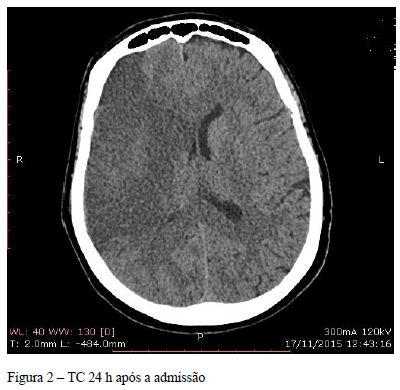

Após algumas horas do início do tratamento, sente-se melhor, sem náuseas ou vômitos e aceita dieta oferecida. Resultado dos exames nesse momento: glicemia 162 mg, Na 142 mEq/l, K 4,3 mEq/l, fosfato 3,8 mEq/l e pH 7,31.